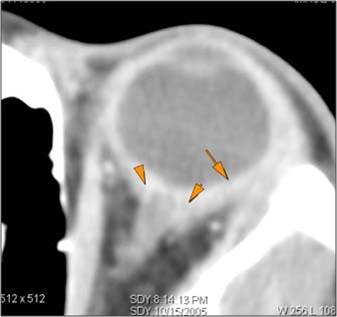

There is a subperiosteal abscess or edema along the medial wall, roof or floor of the orbit. [Yes/No]

The extraocular muscles are swollen or otherwise abnormal. [Yes/No]

There is bone erosion along the walls of the orbit. [Yes/No]

The intraconal orbital fat is infiltrated. [Yes/No]

The orbital apex and the superior and inferior orbital fissures are infiltrated. [Yes/No]

The superior and/or inferior ophthalmic veins are dilated or thrombosed. [Yes/No]